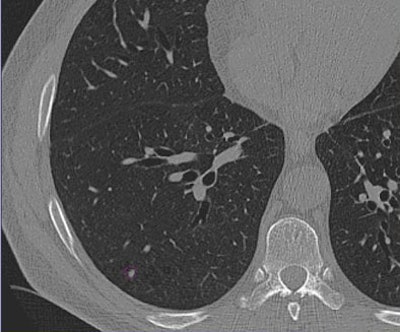

![]() |

| Images of solid lung nodules include uncompressed CT data (above), 24:1 compression (below), 48:1 compression (next down), and 96:1 compression (bottom). CAD detection performance of solid lung nodules greater than 4 mm in size did not suffer until 48:1 compression, and was found to be robust up to 96:1 even when the subjective visual appearance of the compressed images was degraded. The results suggest that 3D lossy wavelet compression can be performed without significant loss of CAD detection performance, which can minimize data storage and ultimately facilitate the implementation of CAD technology in a PACS environment. Images courtesy of Philippe Raffy, Ph.D. |